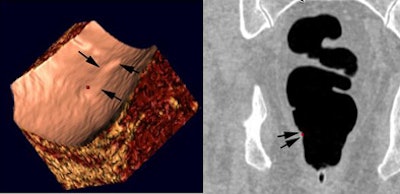

![]() |

| CAD can hurt: Before CAD, a reader correctly dismissed redundant mucosa in the rectum (hemorrhoid). However, after CAD incorrectly marked the finding as positive, the reader incorrectly reported it as a small rectal polyp. |